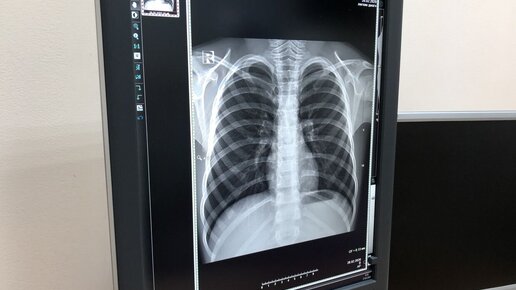

Эффект матового стекла в легких у взрослых – что это такое и насколько серьезно?

Одним из симптомов, указывающих на поражение легких и пневмонию вирусного генеза, является эффект матового стекла в легких у взрослых, определяемый по данным КТ. Но важно понимать, что это признак не только коронавируса. Пандемия COVID-19 ввела в оборот врачей новые термины, которые ранее не были знакомы пациентам. Так, при описании рентгенограмм, полученных после компьютерной томографии легких, врачи обратили внимание на одну особенность - эффект матового стекла, возникающий в ткани легких, пораженных воспалением...